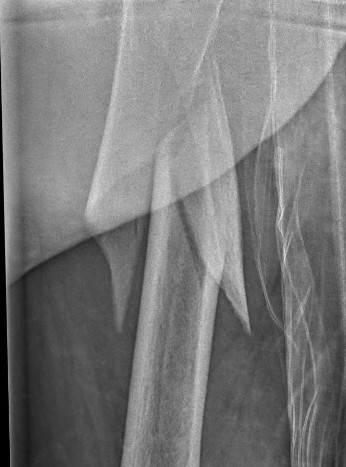

2. Longer spiral fractures

- clamping and cerclage wiring with longer spiral fractures

- clamp assisted reduction of displaced subtrochanteric fractures

- all fractures within 5 degrees of anatomical in two planes

- 43/44 fracture united

Kim et al Eur J Trauma Emerg Surg 2022

- systematic review of 14 studies and 1700 patients

- faster union and better outcome scores with cerclage wiring

- no difference in non union rates